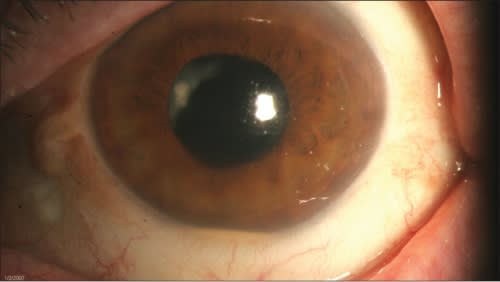

Three months after the pars plana vitrectomy, the patient was referred to our institution complaining of cloudy vision in the left eye for nine days. Examination of the left eye demonstrated 20/60 best-corrected visual acuity (BCVA), dense vitritis, a small hypopyon and a white plaque within the capsular bag (Figure 1). A pretreatment clinical diagnosis of P. acnes endophthalmitis was made.

Figure 1. Three months following initial pars plana vitrectomy, the patient presented to our institution with a small hypopyon and a white plaque involving the posterior capsule. Visual acuity was 20/60.